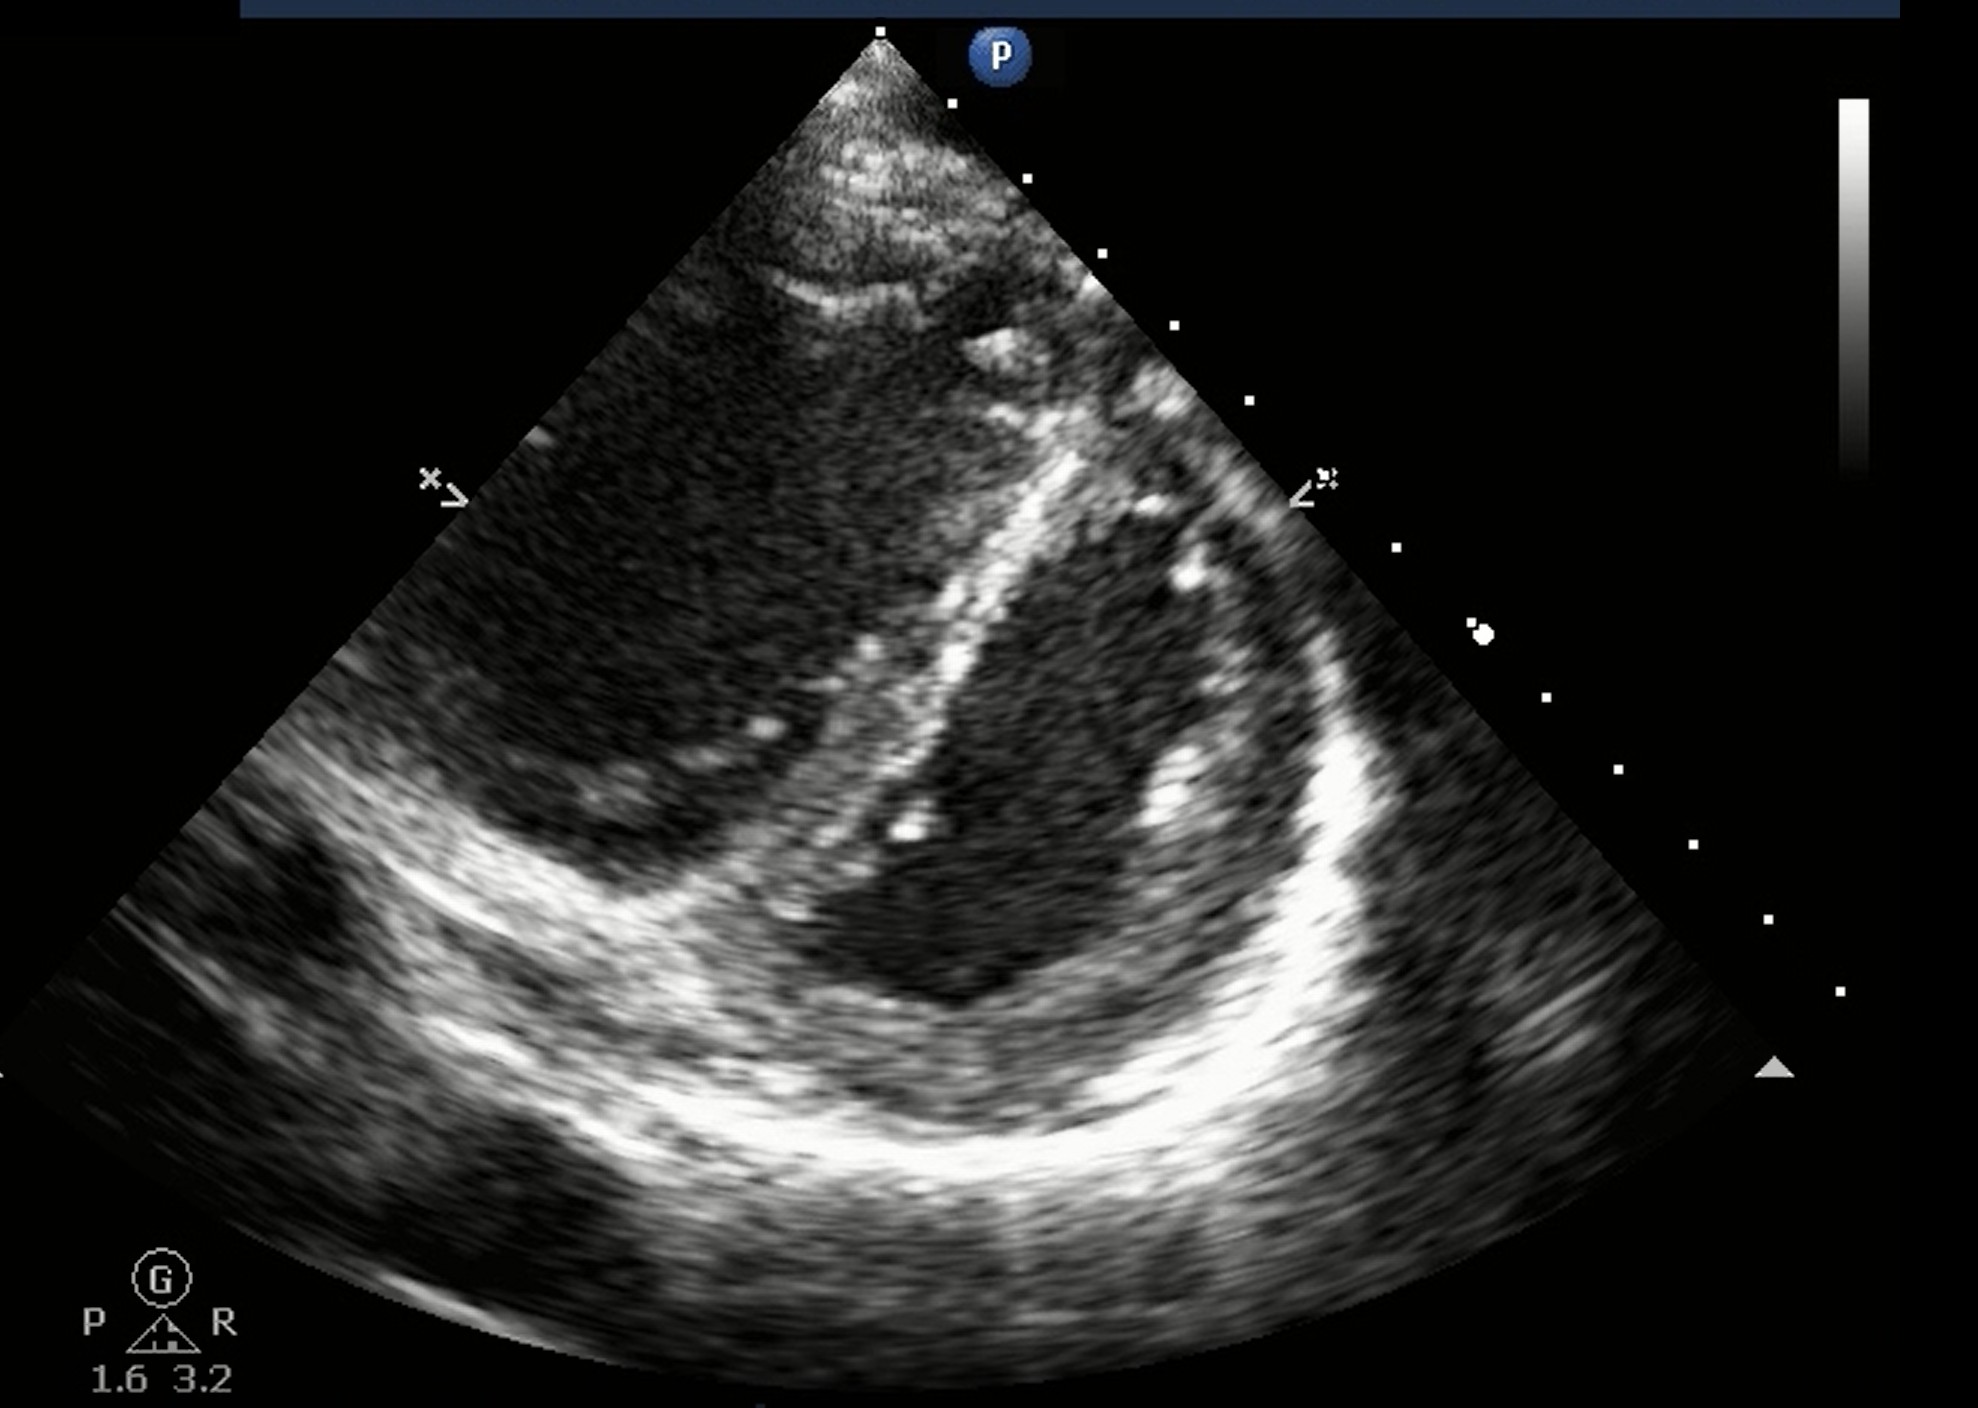

Figure 1 Published May 18, 2020 at 1978 × 1408 in Do It With Heart: Pre-Intubation Point-of-Care Echocardiography for Hemodynamic Optimization Figure 1. D-sign. Interventricular septum is flattened during diastole and forms D-shaped left ventricle.